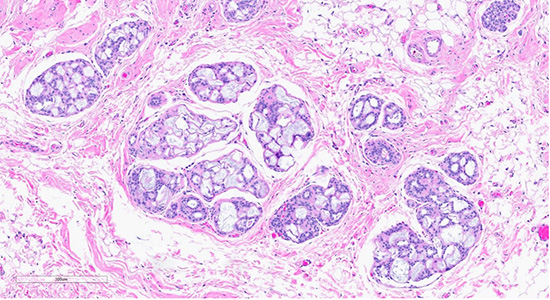

Figure 1: Microscopic slides of collagenous/mucinous spherulosis. Low-power (10× objective) H&E-stained section (top) shows cribriform architecture with collagenous/mucinous spherulosis. High-power (40× objective) H&E-stained section (bottom) demonstrates further detail, with myoepithelial cells surrounding round collagenous/mucinous spherules filled with intraluminal acellular basement membrane material.

Histological examination revealed lobules containing cells arranged in a cribriform pattern with eosinophilic to basophilic, round to oval, collagen-rich spherules (in this case mucinous spherules - may be called mucinous spherperolosis instead). Adjacent regions demonstrated a monomorphic proliferation of mildly atypical cells with round nuclei, indistinct nucleoli, and dyshesive features, along with intracytoplasmic lumina. Other foci were composed of ducts with monomorphic cells displaying ovoid to rounded nuclei in a solid and cribriform pattern, each focus measuring less than 2 mm. A focal area displayed ducts filled with polymorphous cells with peripheral elongated clefts. Additional ducts exhibited an architecturally “flat” pattern without cytologic atypia. The epithelial lining cells were predominantly columnar, with elongated nuclei oriented perpendicular to the basement membrane.

Collagenous spherulosis (CS) is a rare, benign intraductal proliferative lesion of the breast1. It arises from the proliferation of basement membrane material, forming luminal hyaline spherules (eosinophilic to basophilic, occasionally mucoid, like this current case), surrounded by myoepithelial cells. These spherules contain a mixture of basement membrane components, banded collagen, and mineral deposits1.